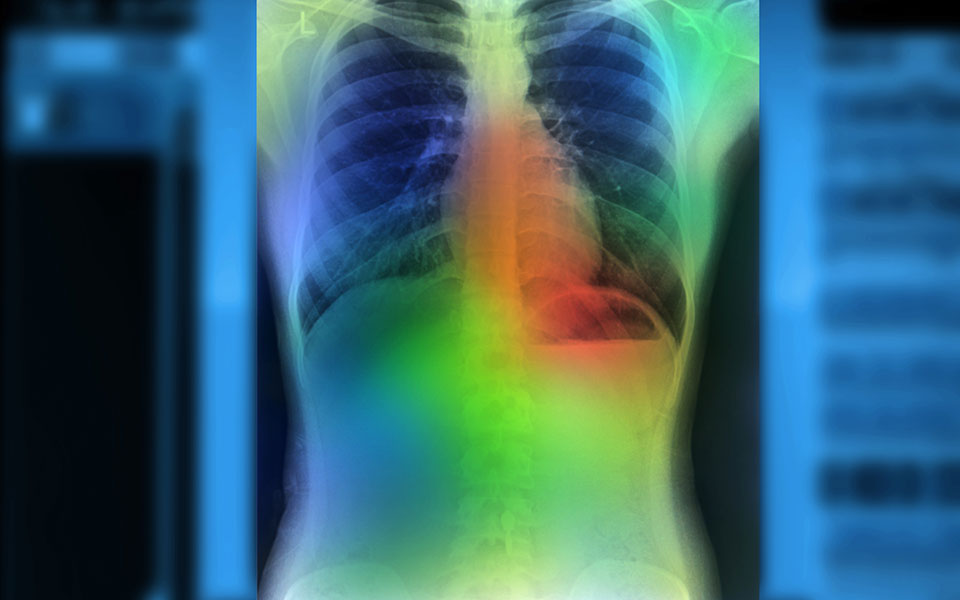

«Στον τομέα της διάγνωσης του καρκίνου του μαστού, η τεχνητή νοημοσύνη μπορεί να επεξεργαστεί εκατομμύρια δεδομένα από προηγούμενες μαστογραφίες των τελευταίων δέκα ετών και να δημιουργήσει αλγορίθμους και λογικές που αναπαράγουν τις καλύτερες πρακτικές στον τομέα. Στόχος είναι επομένως μέσω της τεχνητής νοημοσύνης να έχουμε μία πολύ ασφαλέστερη και ακριβέστερη διάγνωση του ασθενούς, η οποία θα μπορούσε να χρησιμοποιηθεί και σε νοσοκομεία όπου δεν υπάρχει η απαραίτητη ειδίκευση», αναφέρει ο καθηγητής του Πανεπιστημίου Paris-Saclay.

«Με τη βοήθεια της τεχνητής νοημοσύνης μπορούμε να στοχεύσουμε καλύτερα τα καρκινικά κύτταρα και να αποφύγουμε τα υγιή, ώστε να έχουμε την ελάχιστη καταστροφή των υγιών κυττάρων που βρίσκονται γύρω από τον καρκίνο. Μέχρι σήμερα η ακτινοθεραπεία σε ασθενείς γίνεται χειροκίνητα από τον γιατρό μέσω επεξεργασίας της αξονικής τομογραφίας. Πλέον όμως οι αλγόριθμοι μπορούν να μας πουν με μεγαλύτερη ακρίβεια πού θα πρέπει το ρομπότ να ρίξει ακριβώς την ακτίνα», αναφέρει ο κ. Παραγιός και προσθέτει πως «μια από τις εφαρμογές που δουλεύουμε στην TheraPanacea κάνει ακριβώς αυτό και σήμερα είναι εγκατεστημένη σε πάνω από 100 νοσοκομεία στον κόσμο (συμπεριλαμβανομένου και του νοσοκομείου «Αλεξάνδρα» στην Ελλάδα).